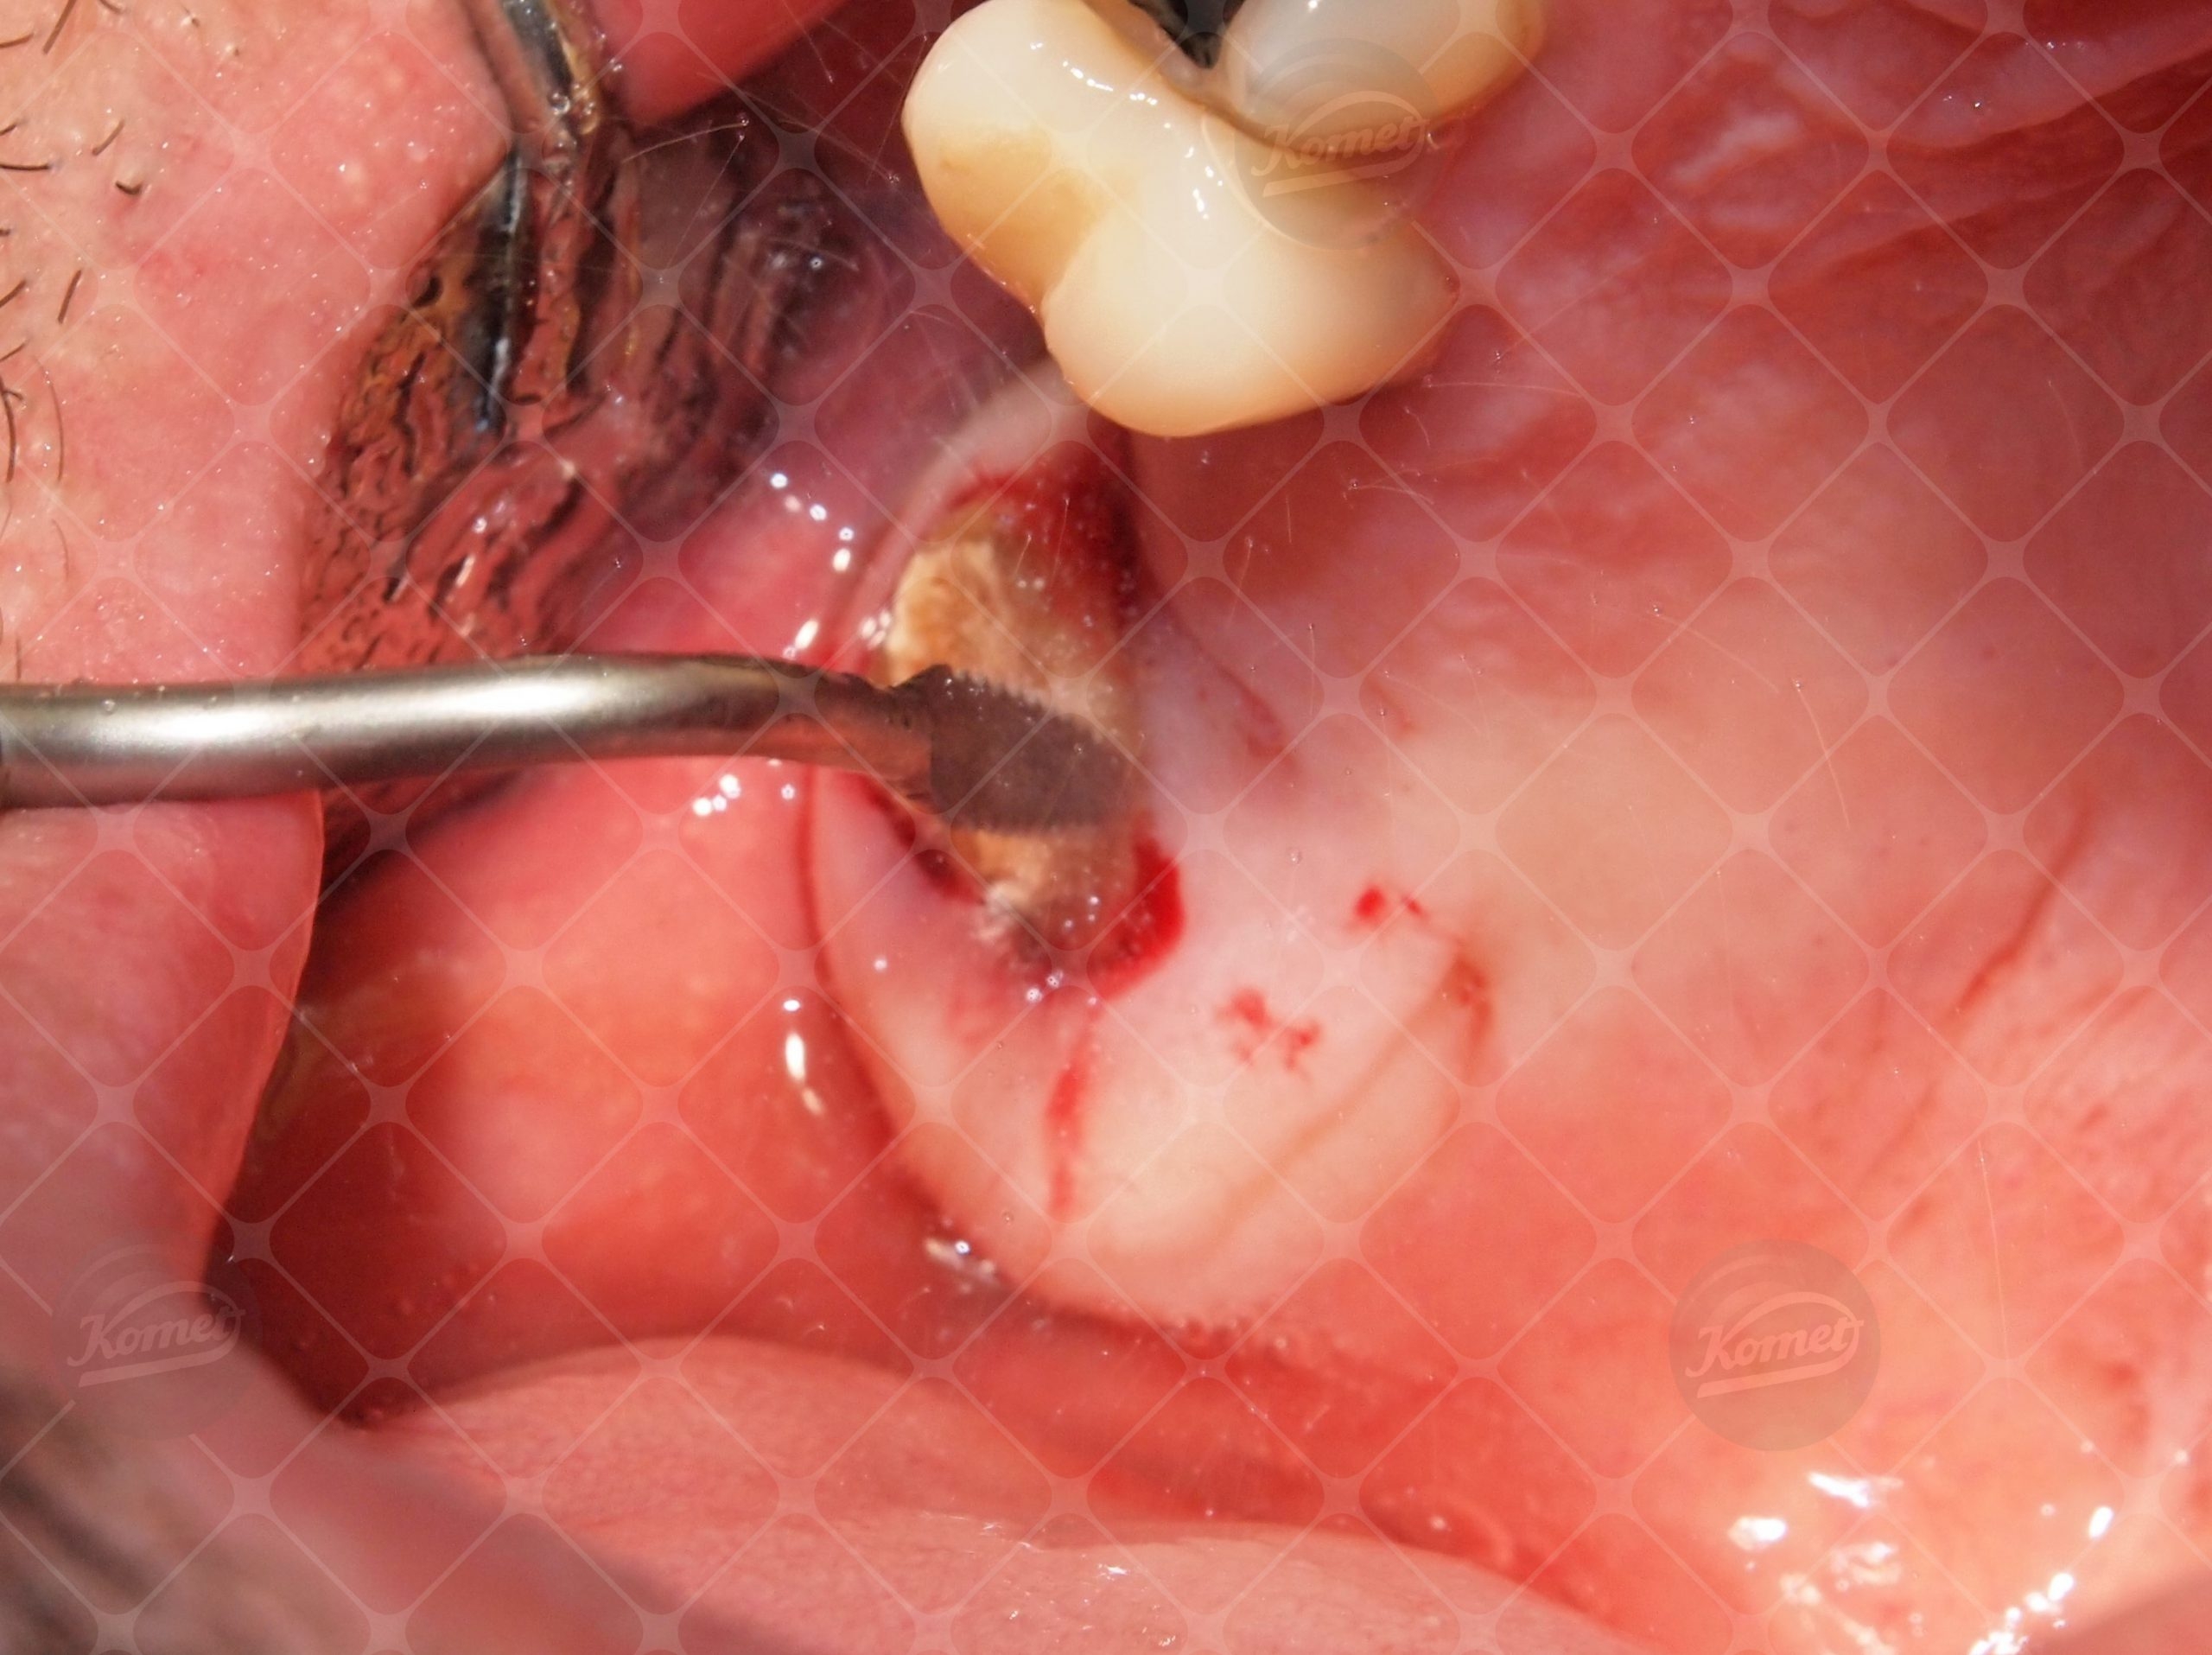

Dopo l'anestesia locale, vengono utilizzate punte soniche per chirurgia micro invasive SFS100 e SFS101 (con irrigazione con soluzione sterile Na Cl da 50 ml/min) per eseguire una sindesmotomia delicata e un taglio micrometrico preciso. Le punte sono guidate con movimenti progressivi attorno ai margini del dente. Con una leggera pressione sull'impugnatura, dopo alcuni secondi si ottiene un’osteotomia peri-radicolare precisa e le radici residue possono essere estratte con un trauma tissutale minimo.

After local anaesthesia , sonic microsaw tips SFS100 & SFS101 are used (under 50 ml /min Na Cl sterile solution irrigation) to perform a delicate sindesmotomy and a precise micrometric cut. Tips are guided with progressive movements around tooth margins. With a gentle pressure application on handle, after some seconds a precise peri-radicular ostectomy is achieved and residual roots can be extracted with minimal tissue trauma.